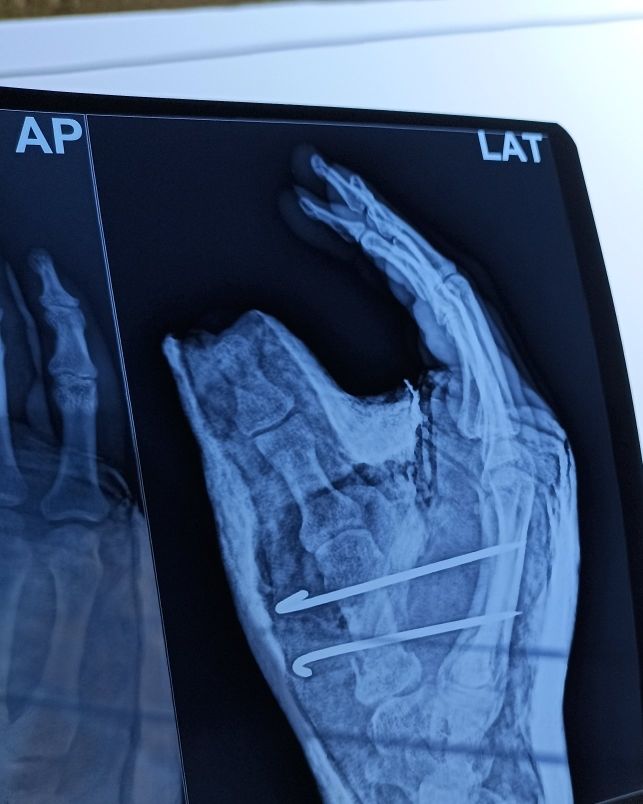

K Wire Procedure . K wire (kirschner wire) is passed through the skin then transversely through the bone and out the other side of the limb. K wire fixation of hand fractures. The wire is then attached to some form of traction so that the pull is applied directly to bone. Introduced in 1909 by martin kirschner, the. They can be placed percutaneously (through the skin) or can be buried beneath the skin. Each method has its advantages and disadvantages. These wires can be drilled through the bone to hold the fragments in place.

These wires can be drilled through the bone to hold the fragments in place. Introduced in 1909 by martin kirschner, the. They can be placed percutaneously (through the skin) or can be buried beneath the skin. K wire fixation of hand fractures. K wire (kirschner wire) is passed through the skin then transversely through the bone and out the other side of the limb. Each method has its advantages and disadvantages. The wire is then attached to some form of traction so that the pull is applied directly to bone.

K Wire Procedure Introduced in 1909 by martin kirschner, the. Each method has its advantages and disadvantages. The wire is then attached to some form of traction so that the pull is applied directly to bone. They can be placed percutaneously (through the skin) or can be buried beneath the skin. K wire (kirschner wire) is passed through the skin then transversely through the bone and out the other side of the limb. Introduced in 1909 by martin kirschner, the. These wires can be drilled through the bone to hold the fragments in place. K wire fixation of hand fractures.